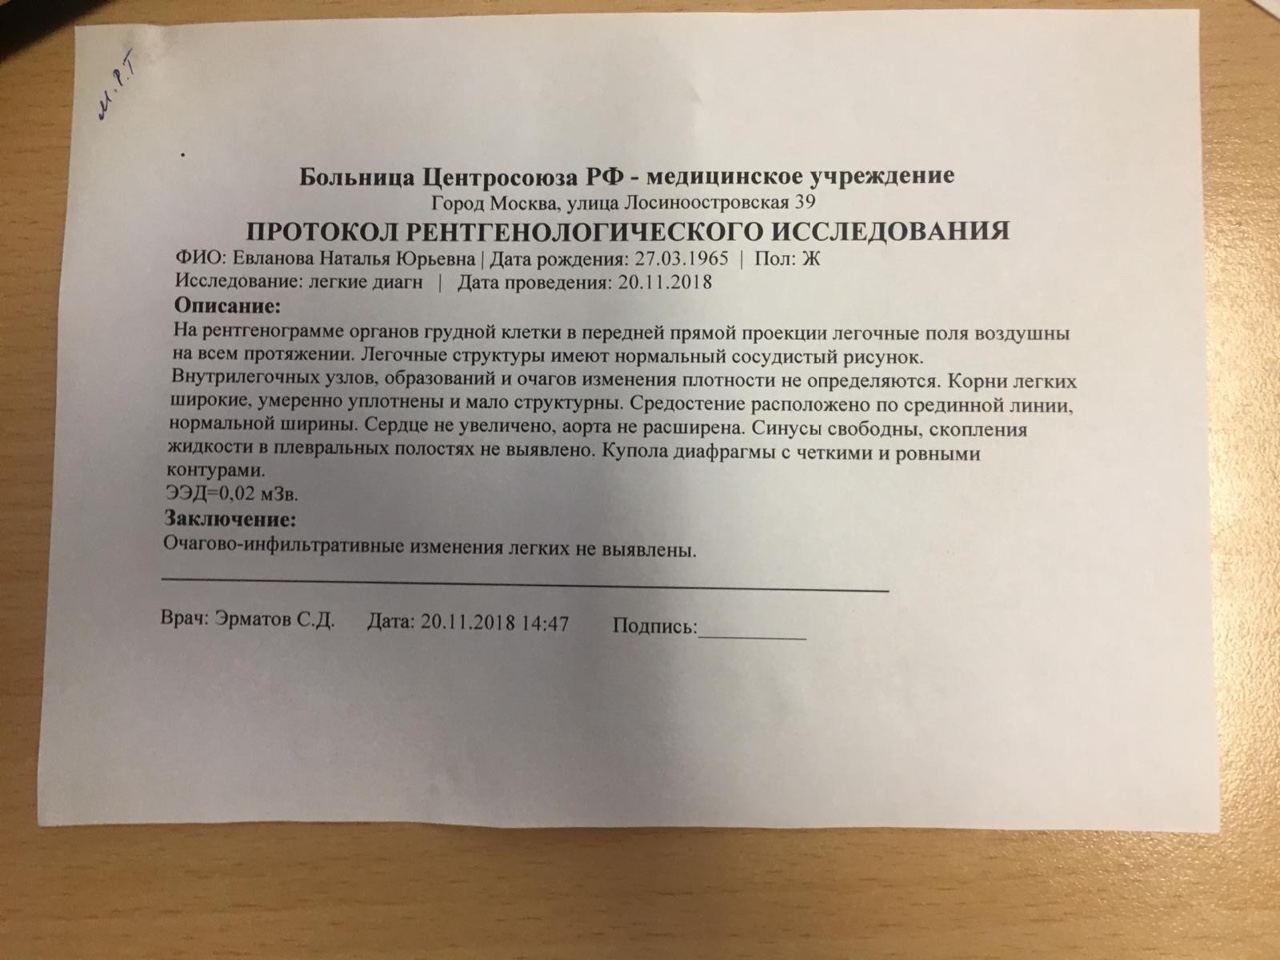

Фотографии рентгеновских снимков без необходимости направления от врача